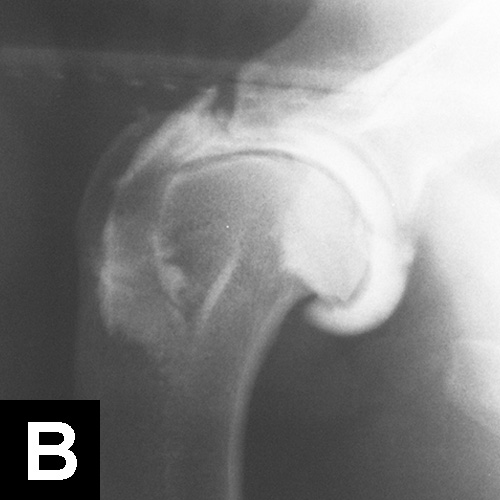

This pathology has a multifactorial etiology that affects the coxofemoral joint, most commonly in large-breed dogs (especially the German shepherd dog), but can also affect small-breed dogs and cats. Genetic and environmental factors can lead to joint laxity, which subsequently causes abnormal development of the acetabulum and femoral head, ultimately resulting in OA. Diagnosis in young patients is based on clinical signs (eg, difficulty in rising, swinging of the hindlimbs, pain, subluxation and laxity of the femoral head [Ortolani test]). Radiographic findings that confirm hip dysplasia are joint subluxation, incongruency, and early degenerative changes (Figure 1).

Figure 1. Ventrodorsal radiograph of the pelvis in a 12-month-old Labrador retriever with bunny-hopping and pain on extension of the hips. Bilateral coxofemoral subluxation and mild OA are evident.